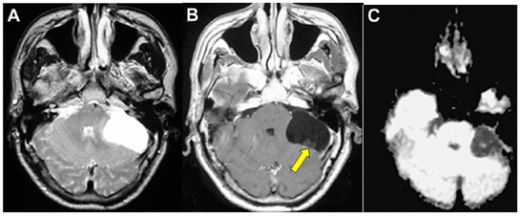

Beyinde kitle ameliyatı, genellikle tümörler, kist veya diğer anormal oluşumların cerrahi olarak çıkarılması amacıyla yapılan bir işlemdir. Bu tür bir ameliyat, beyin dokusuna doğrudan müdahale gerektiği için belirli riskler taşır ve sonrasında hastalar için çeşitli zorluklar ortaya çıkabilir. İşte bu makalede, beyin kitle ameliyatının riskleri ve sonrası hakkında detaylı bir inceleme yapılacaktır. 1. Beyin Kitle Ameliyatının Riskleri Beyin kitle ameliyatı, birçok risk barındırır. Bu riskler arasında şunlar bulunmaktadır:

4. Potansiyel Komplikasyonlar Ameliyat sonrası komplikasyonlar, hastanın genel sağlığını etkileyebilir. Bunlar arasında:

Beyin ödemi gibi komplikasyonlarla karşılaşanlar için, bu durumu aşmak için çeşitli yöntemler bulunuyor. Fiziksel terapi, doktor önerileri doğrultusunda düzenli olarak yapılmalı ve gerektiğinde psikolojik destek de alınmalıdır. Bu tür durumlar, destek gruplarına katılarak veya benzer deneyimleri yaşamış insanlarla iletişim kurarak daha kolay aşılabilir. Bu süreçte, kendinize karşı nazik olmalı ve iyileşme sürecine zaman tanımalısınız.